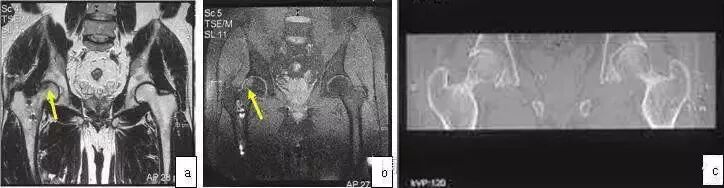

9、强直性脊柱炎累及双髋

此病多累及青少年男性,双髋关节间隙变窄但股骨头仍呈圆形。此类患者常应用激素治疗,即使伴有股骨头坏死,股骨头塌陷仍较少见。化验检查HLA-B27⊕,X线片示骶髂关节变窄或消失,脊柱强直,因此鉴别不难。